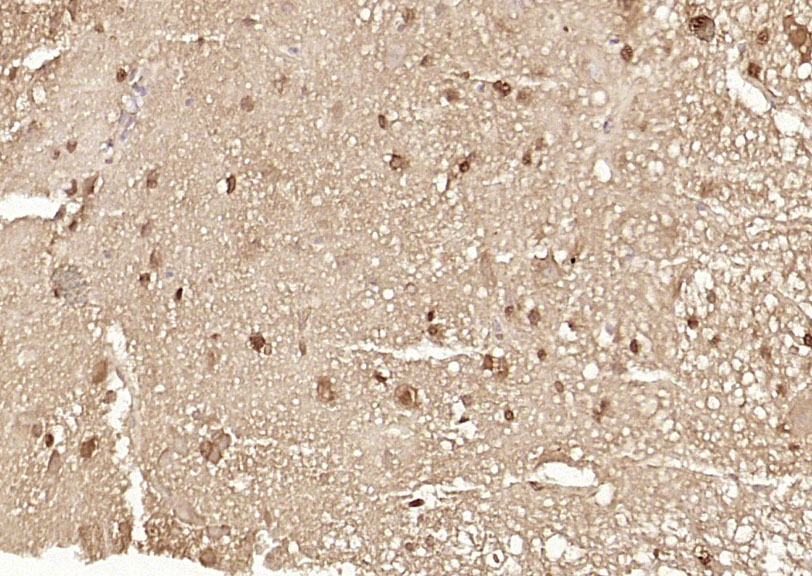

Paraformaldehyde-fixed, paraffin embedded (rat brain); Antigen retrieval by boiling in sodium citrate buffer (pH6.0) for 15min; Block endogenous peroxidase by 3% hydrogen peroxide for 20 minutes; Blocking buffer (normal goat serum) at 37°C for 30min; Antibody incubation with (Ataxin 7) Polyclonal Antibody, Unconjugated (bs-11318R) at 1:200 overnight at 4°C, followed by operating according to SP Kit(Rabbit) (sp-0023) instructionsand DAB staining.